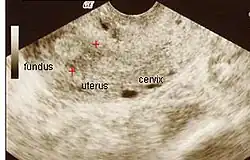

Ultrasound view.

The history of a pregnancy event followed by a D&C leading to secondary amenorrhea or hypomenorrhea is typical. Hysteroscopy is the gold standard for diagnosis.[18] Imaging by sonohysterography or hysterosalpingography will reveal the extent of the scar formation. Ultrasound is not a reliable method of diagnosing Asherman's Syndrome. Hormone studies show normal levels consistent with reproductive function.